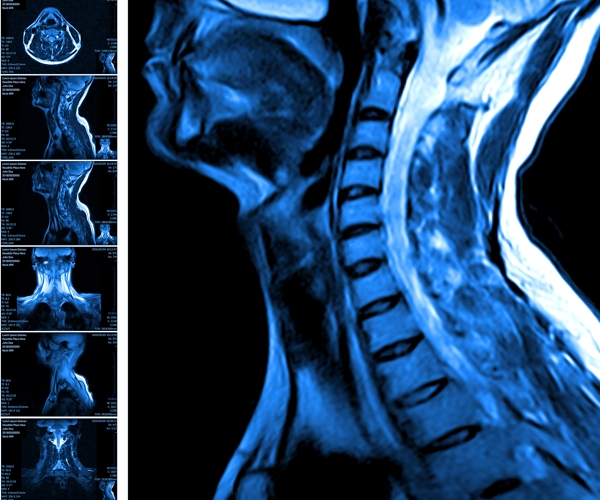

La Risonanza Magnetica Nucleare è un esame non invasivo, che non si avvale di radiazioni, e come indagine diagnostica è indicata per lo studio dei tessuti (sistema nervoso, cuore, addome, colonna e articolazioni). Può essere eseguita, a seconda delle indicazioni, con o senza mezzo di contrasto. È una moderna tecnica d'analisi che si basa su radiofrequenze e campi magnetici, fornisce immagini molto dettagliate e ad elevato contrasto e, a differenza della TAC - Tomografia Assiale Computerizzata, è in grado di evidenziare anche minime differenze strutturali, senza l'impiego di radiazioni ionizzanti. Il Servizio di Diagnostica per Immagini della PacC è dotato di una Risonanza Magnetica ad Alto Campo da 1,5 Tesla di ultima generazione in grado di effettuare indagini di alta qualità. La notevole esperienza dei specialisti, dei tecnici e del personale sanitario permette una diagnosi puntuale e accurata. La Risonanza Magnetica ad Alto Campo è una nuova tipologia di risonanza che si basa su un campo magnetico statico elevato; il cambiamento maggiore rispetto alle tecniche precedenti è caratterizzato dal mutamento delle modalità di studio. È un esame indolore e al quale tutti possono essere sottoposti fatta eccezione i pazienti portatori di pace-maker, neurostimolatori, protesi con circuiti elettronici o placche metalliche interne dovute ad interventi precedenti. L'esame può durare, a seconda della tipologia, dai 40 a i 60 minuti.Al PacC si eseguono Risonanze Magnetiche a diversi distretti ad esempio: